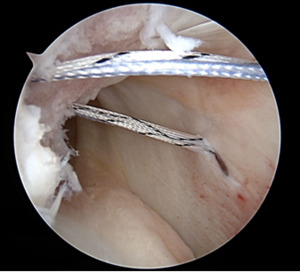

I have learned to recognize that bone loss, Hill Sachs lesions (Image 1), off-track lesions, three (or more) dislocations, ALPSA lesions, male gender, hyperlaxity, and collision sports all stratify patients into higher risk for failure.

To combat these problems, I now use more anchors and mattress suture patterns. I often plicate the posterior inferior capsule, even when the tear doesn’t extend around the back. I have also learned, after training, how to execute a well-done open capsule shift and a Latarjet procedure. Although it has been close to 20 years since Eugene Wolf coined “Hill Sachs Remplissage”, this procedure has become increasingly popular as evidenced by the histogram spike in pub med publications using the word remplissage.(Image 2,3)